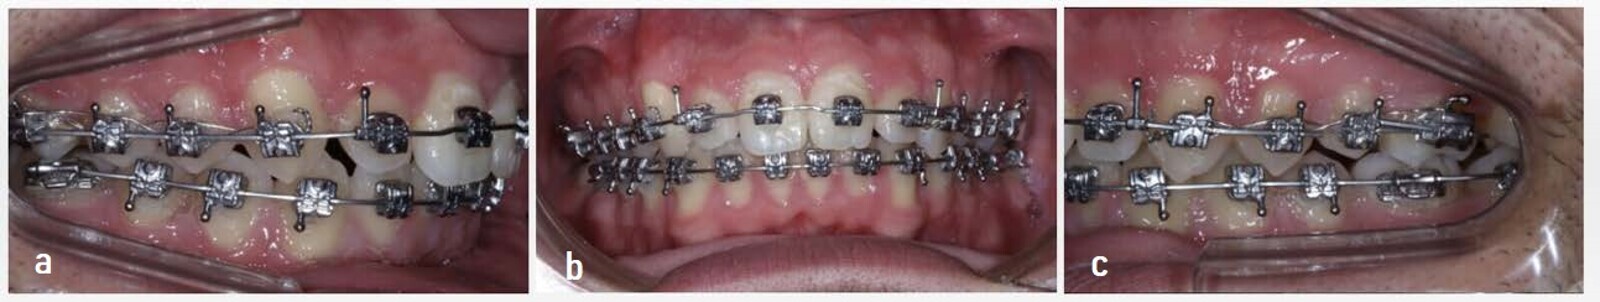

After removing the Class II CMA, we used the Carriere SLX Bracket System (Henry Schein Orthodontics) in both arches with a 0.014 in. copper nickel–titanium (NiTi) archwire. The maxillary arch was undertied from the molar to the canine in both quadrants in order to retain the previously obtained results. In turn, we started using Class II short 2.5 oz, 3/16 in. elastics for night-time use until a Class I occlusion had been established (Fig. 13). The archwire sequence was 0.014 × 0.025 in. and 0.017 × 0.025 in. copper NiTi, finishing with 0.019 × 0.025 in. CNA.

The use of Class II elastics and posterior box elastics helped to achieve the correct occlusion in both arches. Crimpable hooks were placed distal to each maxillary lateral incisor in the strongest archwire (0.019 × 0.025 in. CNA). This facilitated the distalisation of the anterior sector through a power chain placed in the tooth #15–14 hook and tooth #25–24 hook positions. This did not touch the canine so that the traction caused by the elastic would not disrupt the Class I canine relationship that had been achieved (Fig. 14). In the final stages, owing to the inability to fit tooth #25 correctly, the distal archwire of the first premolar was cut to facilitate the action of the elastics and achieve some contact between the tooth and its antagonist (Fig. 15).

One year after placement of the fixed appliances, the treatment concluded (Figs. 16 & 17). Removable transparent retainers were manufactured to maintain the results. Considering the treatment stage with the CMA and the subsequent stage with the fixed multi-bracket appliances, the total time needed for the correction was one year and seven months.